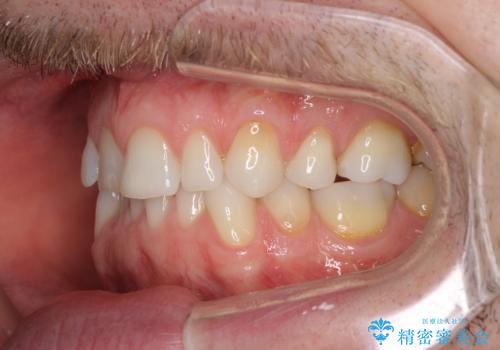

- 上下前歯の叢生を気にして来院された患者様です。

抜歯矯正をした後戻りということで、歯列不正はそれほど大きくなかったため、インビザライン・ライトを用いて矯正治療を行うこととしました。

前歯のデコボコが残っており、シミュレーション通りに動いていない部分がありましたが、再矯正であることやご本人の満足いくところまでデコボコが改善されたとのことで、治療を終了することとしました。